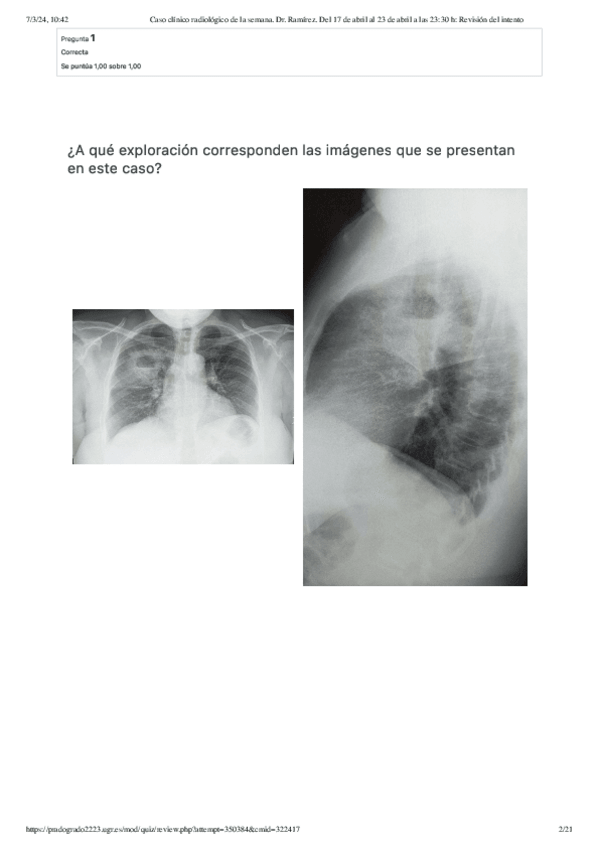

He publicado nuevos apuntes de 4º Radiología y Medicina Física: Caso-clinico-radiologico-de-la-semana.-Dr.-Ramirez.-Del-17-de-abril-al-23-de-abril-a-las-2330-h-Revision-del-intento.pdf

21 páginas